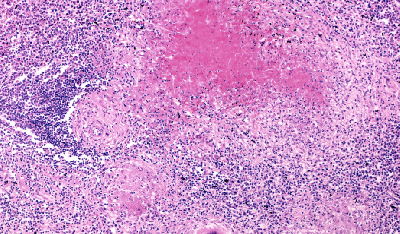

В России в 2024 году выявлено наибольшее число случаев туберкулеза среди стран Европейского региона ВОЗ. Но по числу случаев на 100 тыс. населения первые места занимают Украина, Таджикистан, Азербайджан и Молдавия.Всемирная организация здравоохранения (ВОЗ) и Европейский центр по контролю и профилактике заболеваний (ECDC) опубликовали отчет по надзору и мониторингу туберкулеза. Документ охватывает данные 53 стран в Европе и Центральной Азии, которые относятся к Европейскому региону ВОЗ.

Согласно отчету, в России в 2024 году зарегистрировано самое большое число случаев туберкулеза — 49 тыс. или 34 случая на 100 тыс. населения. При этом по заболеваемости на 100 тыс. населения на первом месте в Европе находится Украина (86 случаев). За ней следуют Таджикистан (75 случаев), Азербайджан и Молдавия (по 64 случая). В России выявлено 14 236 случаев легочной формы туберкулеза с множественной лекарственной устойчивостью (у 45,4% пациентов).

Распространенность заболевания с множественной лекарственной устойчивостью в Европе значительно превышает общемировой показатель (23% в сравнении с 3,2%). Около половины (51%) ранее леченных случаев заболевания устойчивы к рифампицину. В мире этот показатель составляет только 16%.